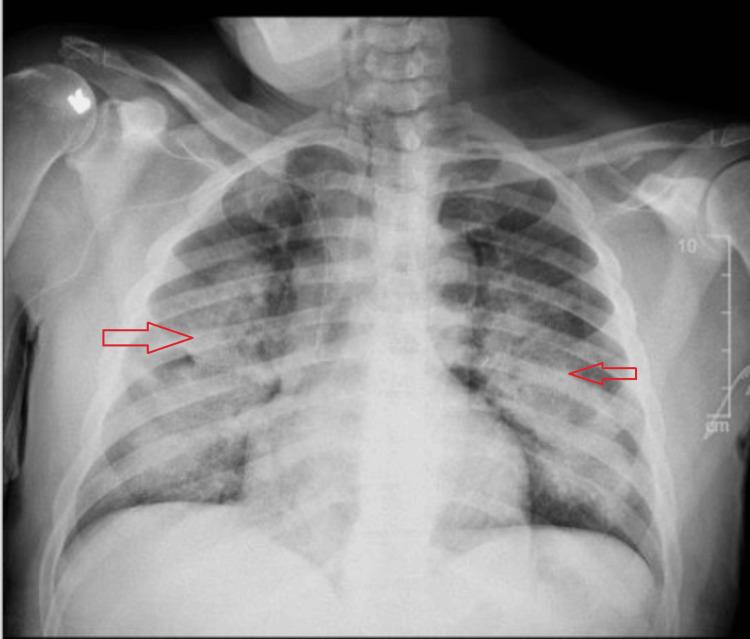

Pulmonary infiltrates, arising from diverse etiologies such as infections, cardiac conditions, or parenchymal diseases, present a diagnostic challenge. Drug-induced pneumonitis, although less common, should be considered, especially when symptoms develop after medication initiation. This case report highlights a rare yet significant complication of antibiotic therapy, daptomycin-induced eosinophilic pneumonia (DIEP). A 56-year-old male with a history of type 2 diabetes mellitus, hypertension, and renal insufficiency presented with pleuritic chest pain and a productive cough for two days. Chest X-ray and CT imaging revealed bilateral scattered airspace opacities and ground-glass opacities, suggesting pneumonia or pulmonary edema. Initially treated for healthcare-associated pneumonia, the patient's condition persisted despite therapy. His medical history included osteomyelitis treated with vancomycin, later switched to daptomycin. Two weeks after the switch, the patient developed new respiratory symptoms. A bronchoalveolar lavage (BAL) was performed to establish the diagnosis of eosinophilic pneumonia. BAL showed >25% eosinophils, confirming daptomycin-induced eosinophilic pneumonia. The antibiotic was discontinued, and prednisone 40 mg daily was initiated, leading to the resolution of symptoms. Daptomycin, an antibiotic commonly used to treat gram-positive infections, can rarely cause eosinophilic pneumonia, a rare adverse reaction characterized by pleuritic chest pain, dyspnea, and diffuse ground-glass opacities on imaging. The mechanism remains unclear but may involve surfactant binding, leading to alveolar epithelial injury. Diagnosis is confirmed through BAL, with eosinophilia greater than 25%. Management consists of discontinuing daptomycin and initiating steroids if necessary. This case underscores the importance of early recognition and prompt discontinuation of the offending drug, along with the use of steroids in cases with severe symptoms. BAL is a key diagnostic tool in confirming drug-induced eosinophilic pneumonia. In conclusion, daptomycin-induced eosinophilic pneumonia is a rare but significant complication requiring vigilance in patients treated with the drug. Early diagnosis and effective management are crucial for achieving favorable outcomes.

肺部浸润由多种病因引起,如感染、心脏疾病或实质性疾病,这给诊断带来了挑战。药物性肺炎虽不太常见,但也应予以考虑,尤其是在用药后出现症状的情况下。本病例报告强调了抗生素治疗一种罕见但严重的并发症,即达托霉素诱导的嗜酸性粒细胞性肺炎(DIEP)。一名56岁男性,有2型糖尿病、高血压和肾功能不全病史,出现胸膜炎性胸痛和咳痰2天。胸部X线和CT成像显示双侧散在的气腔实变和磨玻璃影,提示肺炎或肺水肿。最初按医疗保健相关肺炎进行治疗,尽管进行了治疗,患者病情仍持续。他的病史包括用万古霉素治疗的骨髓炎,后来改用达托霉素。换药两周后,患者出现了新的呼吸道症状。进行了支气管肺泡灌洗(BAL)以确诊嗜酸性粒细胞性肺炎。BAL显示嗜酸性粒细胞>25%,证实为达托霉素诱导的嗜酸性粒细胞性肺炎。停用抗生素,并开始每日服用40mg泼尼松,症状得以缓解。达托霉素是一种常用于治疗革兰氏阳性感染的抗生素,很少会引起嗜酸性粒细胞性肺炎,这是一种罕见的不良反应,其特征为胸膜炎性胸痛、呼吸困难以及影像学上的弥漫性磨玻璃影。其机制尚不清楚,但可能涉及表面活性剂结合,导致肺泡上皮损伤。通过BAL确诊,嗜酸性粒细胞增多大于25%。处理措施包括停用达托霉素,必要时开始使用类固醇。本病例强调了早期识别和及时停用致病药物的重要性,以及在症状严重的病例中使用类固醇的重要性。BAL是确诊药物性嗜酸性粒细胞性肺炎的关键诊断工具。总之,达托霉素诱导的嗜酸性粒细胞性肺炎是一种罕见但严重的并发症,在用该药物治疗的患者中需要保持警惕。早期诊断和有效管理对于取得良好预后至关重要。